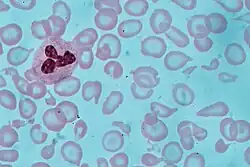

Anemia is typically diagnosed on a complete blood count. Apart from reporting the number of red blood cells and the hemoglobin level, the automatic counters also measure the size of the red blood cells by flow cytometry, which is an important tool in distinguishing between the causes of anemia. Examination of a stained blood smear using a microscope can also be helpful, and it is sometimes a necessity in regions of the world where automated analysis is less accessible.

If an automated count is not available, a reticulocyte count can be done manually following special staining of the blood film. In manual examination, activity of the bone marrow can also be gauged qualitatively by subtle changes in the numbers and the morphology of young RBCs by examination under a microscope. Newly formed RBCs are usually slightly larger than older RBCs and show polychromasia. Even where the source of blood loss is obvious, evaluation of erythropoiesis can help assess whether the bone marrow will be able to compensate for the loss and at what rate.

Other characteristics visible on the peripheral smear may provide valuable clues about a more specific diagnosis; for example, abnormal white blood cells may point to a cause in the bone marrow.

Macrocytic anemia can be further divided into "megaloblastic anemia" or "nonmegaloblastic macrocytic anemia". The cause of megaloblastic anemia is primarily a failure of DNA synthesis with preserved RNA synthesis, which results in restricted cell division of the progenitor cells. The megaloblastic anemias often present with neutrophil hypersegmentation (six to 10 lobes). The nonmegaloblastic macrocytic anemias have different etiologies (i.e., unimpaired DNA globin synthesis), which occur, for example, with excessive alcohol use. In addition to the nonspecific symptoms of anemia, specific features of vitamin B12 deficiency include peripheral neuropathy and subacute combined degeneration of the cord with resulting balance difficulties from posterior column spinal cord pathology.[82] Other features may include a smooth, red tongue and glossitis. The treatment for vitamin B12-deficient anemia was first devised by William Murphy, who bled dogs to make them anemic, and then fed them various substances to see what (if anything) would make them healthy again. He discovered that ingesting large amounts of liver seemed to cure the disease. George Minot and George Whipple then set about to isolate the curative substance chemically and ultimately were able to isolate the vitamin B12 from the liver. All three shared the 1934 Nobel Prize in Medicine.[83]

A dimorphic appearance on a peripheral blood smear occurs when there are two simultaneous populations of red blood cells, typically of different size and hemoglobin content (this last feature affecting the color of the red blood cell on a stained peripheral blood smear). For example, a person recently transfused for iron deficiency would have small, pale, iron-deficient red blood cells (RBCs) and the donor RBCs of normal size and color. Similarly, a person transfused for severe folate or vitamin B12 deficiency would have two cell populations, but, in this case, the patient's RBCs would be larger and paler than the donor's RBCs.

A person with sideroblastic anemia (a defect in heme synthesis, commonly caused by alcoholism, but also drugs/toxins, nutritional deficiencies, a few acquired and rare congenital diseases) can have a dimorphic smear from the sideroblastic anemia alone. Evidence for multiple causes appears with an elevated RBC distribution width (RDW), indicating a wider-than-normal range of red cell sizes, also seen in common nutritional anemia.